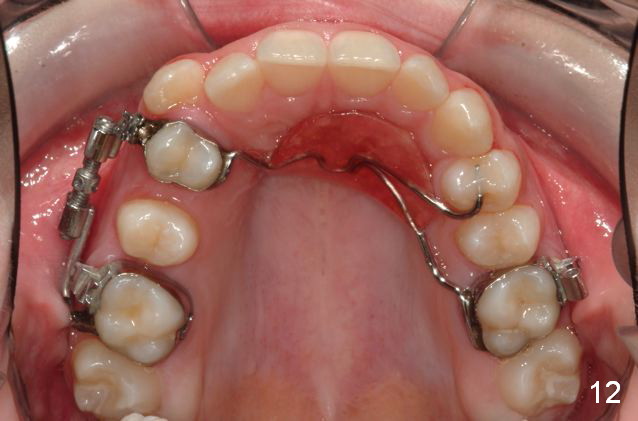

Rapid Molar Distalizer is placed (Fig.11). It is turned twice a week. UR6,7 are bodily distalized to Class I with gaining of the arch length 4 months 11 days later (Fig.12,14) without adverse effect on U midline (Fig.13). Final result?